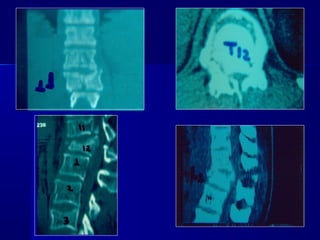

CCTT -- ssccaann

–PPoosstteerriioorr aarrcchh

wweellll ddeeffiinneedd

–RReettrrooppuullsseedd

ffrraaggnneennttss

ccoorrdd -- nneerrvveess

ccoommpprroommiisseedd

–AAddjjaacceenntt lleevveell

iinnjjuurryy –– 1100%%

MMRRII

–UUsseeffuull ttoo eevvaalluuaattee

ddiissccrreeppaannccyy

bbeettwweeeenn cclliinniiccaall

eevvaalluuaattiioonn aanndd xx--

rraayy // CCTT ffiinnddiinnggss

–DDiisscc hheerrnniiaattiioonn

–LLiiggaammeennttoouuss

iinnjjuurryy